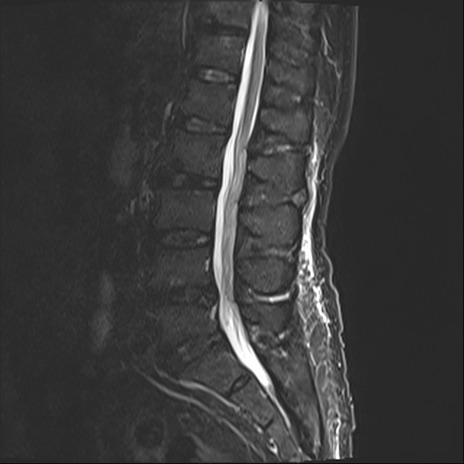

【整形】TIPS症例2 腰椎MRI STIR(矢状断像)

【症例】70歳代男性

【主訴】左下肢痛

【現病歴】2週間前くらいから腰痛、左下肢痛あり。左臀部から大腿、下腿外側のしびれが常時ある。歩行とともに同部位の痛みあり。

【身体所見】Lasegue70-/60+、Bragard-/±、PTR ±/±、ATR -/-、IP 5/5、TA 5/4、TS 5/5、EHL 右第1足趾なし/3、FHL 5/5、hypersthesia(-)、足背動脈触知良好

異常所見と診断は?